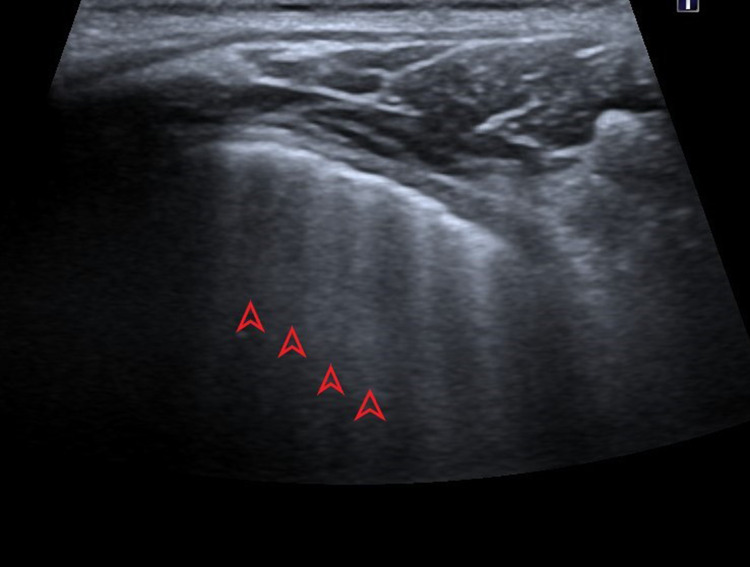

Picture 1.

Ultrasound profile 3, presence of A-lines (red arrows), parallel to horizontal hyperechoic pleural line (pointed red arrow)

(c) A lines—horizontal hyperechoic lines, parallel with a pleural line which represents normal findings.